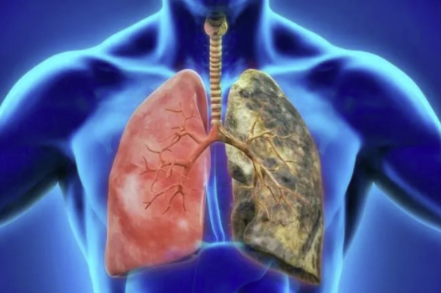

Bronquitis crónica | EPOC El glutatión como regulador clave del estrés oxidativo y la inflamación pulmonar Leer más